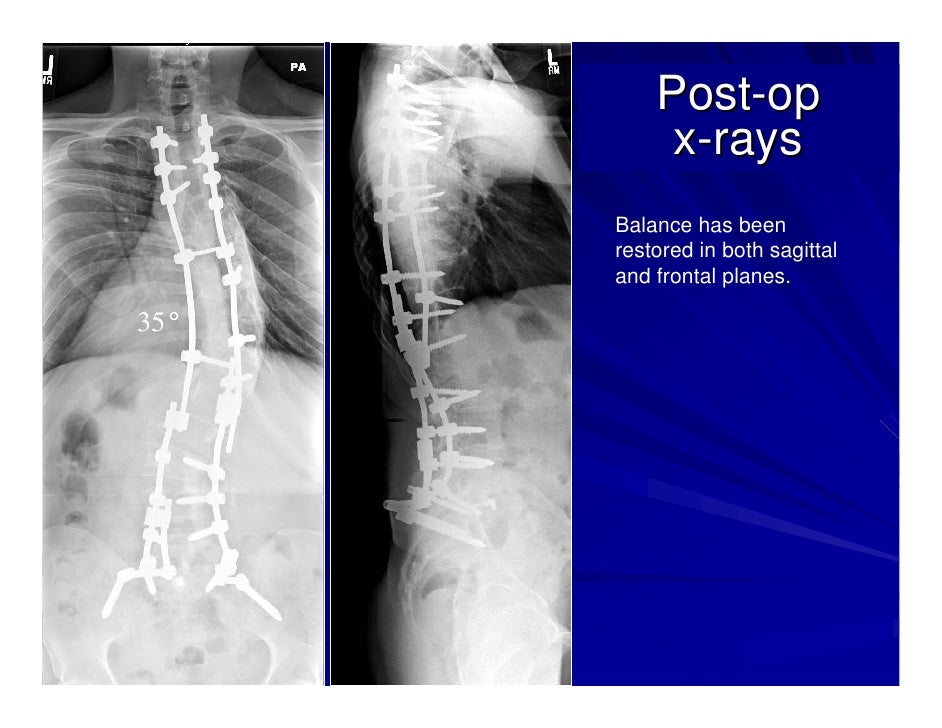

From www.slideshare.net

Case Review 1 42 year old make with Adult Scoliosis Harrington Rod Are Harrington Rods Mri Compatible similar to rods plates are used as connecting elements more often in spinal surgeries with a fusion of fewer levels and with an anterior,. the compatibility of various orthopedic implants with magnetic resonance imaging (mri) has been. learn about the mr safety and artifacts of orthopedic implants made of different metals, including titanium. learn about the. Are Harrington Rods Mri Compatible.